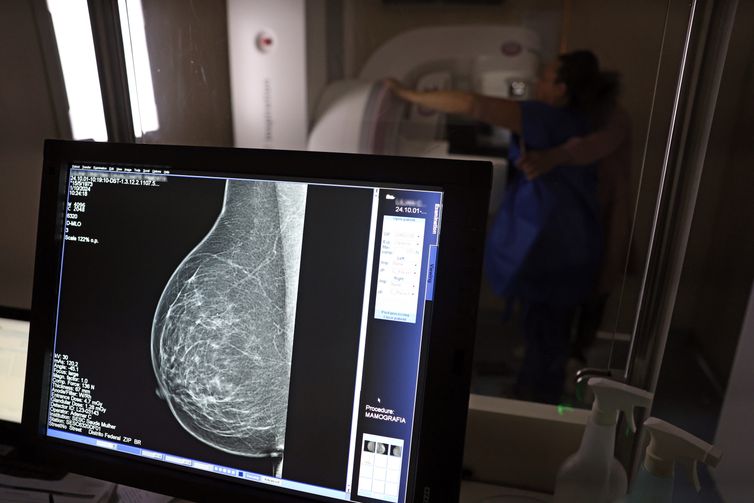

Um dos principais critérios é a realização de rastreamento organizado, ou seja, a convocação das usuárias para realizarem exames regularmente, mesmo sem sintomas. No caso do câncer de mama, a cartilha seguiu o protocolo do Ministério da Saúde e do Instituto Nacional do Câncer (Inca): mamografias a cada dois anos para as mulheres com idades entre 50 e 69 anos.

Elaborado em conjunto pelo Colégio Brasileiro de Radiologia e Diagnóstico por Imagem, Sociedade Brasileira de Mastologia e Federação Brasileira das Associações de Ginecologia e Obstetrícia, o parecer argumenta que em 2024, 22% das mulheres que morreram por câncer de mama no Brasil tinham menos de 50 anos, e 34% tinham mais de 70.

Os estudos reunidos no documento também apontam que houve crescimento de casos de câncer em mulheres mais jovens, e que esses tumores geralmente são mais agressivos e tem mais risco de metástase.

Para as entidades médicas, a mamografia deve incluir essas pessoas, porque o diagnóstico de câncer em pessoas assintomáticas, a partir de exames de imagem, demanda tratamentos que impactam menos a qualidade de vida da paciente, e tem menos risco de recidivas, metástases e mortalidade.

“No grupo do rastreamento, o tumor é detectado no estágio inicial e apresenta características biológicas menos agressivas, permitindo maior número de cirurgias conservadoras da mama. Essas pacientes também possuem menos indicação de quimioterapia, consequentemente com menores efeitos colaterais do tratamento” diz o parecer.

E as entidades complementam: “o diagnóstico precoce também é custo-efetivo e se associa a benefícios econômicos, porque reduz os custos do tratamento, ao evitar terapias caras para cânceres em estágios avançados”.

Mas de acordo com o diretor-geral do Inca, Roberto Gil, não há discussão sobre os benefícios do diagnóstico precoce, mas sim sobre a efetividade de aumentar a idade dos exames de rastreamento, que devem ser feitos por todas as mulheres, quando não há sintomas ou suspeita.

“Nossa questão não está baseada na incidência da doença abaixo dos 50 anos, mas nas fortes evidências de que o rastreamento abaixo de 50 anos não tem sensibilidade, aumentando o risco de sobrediagnóstico e de maior número de intervenções, sobrecarregando todo o sistema de Saúde”, afirmou Gil na quinta-feira (27).

Em entrevista anterior à Agência Brasil, Gil enfatizou: “A informação científica que temos hoje não é da opinião de um especialista, é da literatura médica, avaliada com o nível de evidência 1, meta-análise e estudo randomizado, que é o maior nível de evidência que se tem. Grande parte dos trabalhos não conseguiu mostrar nenhum aumento de sobrevida na faixa dos 40 aos 50 anos. Só houve aumento de sobrevida na faixa de 50 a 69 anos.”

De acordo com ele, isso se explica pela maior densidade da mama de mulheres mais jovens, o que aumenta as chances de um resultado falso positivo, que precisará ser descartado por exames adicionais, ou até por cirurgias desnecessárias.

No Brasil, a cobertura da mamografia ainda é um desafio. A última Pesquisa Nacional de Saúde, realizada pelo Instituto Brasileiro de Geografia e Estatística (IBGE) em 2019, mostrou que menos de 60% das mulheres de 50 a 69 anos tinham feito mamografia há menos de dois anos da data da entrevista.

O parecer ressalta que o cenário do rastreamento é melhor na rede privada, onde “53% dos tumores são detectados pela mamografia, em pacientes assintomáticas, e 40,6% são diagnosticados no estágio I (menos agressivo)”, logo não há risco de prejuízo para as usuárias que já têm indicação, caso mais mulheres sejam incluídas.